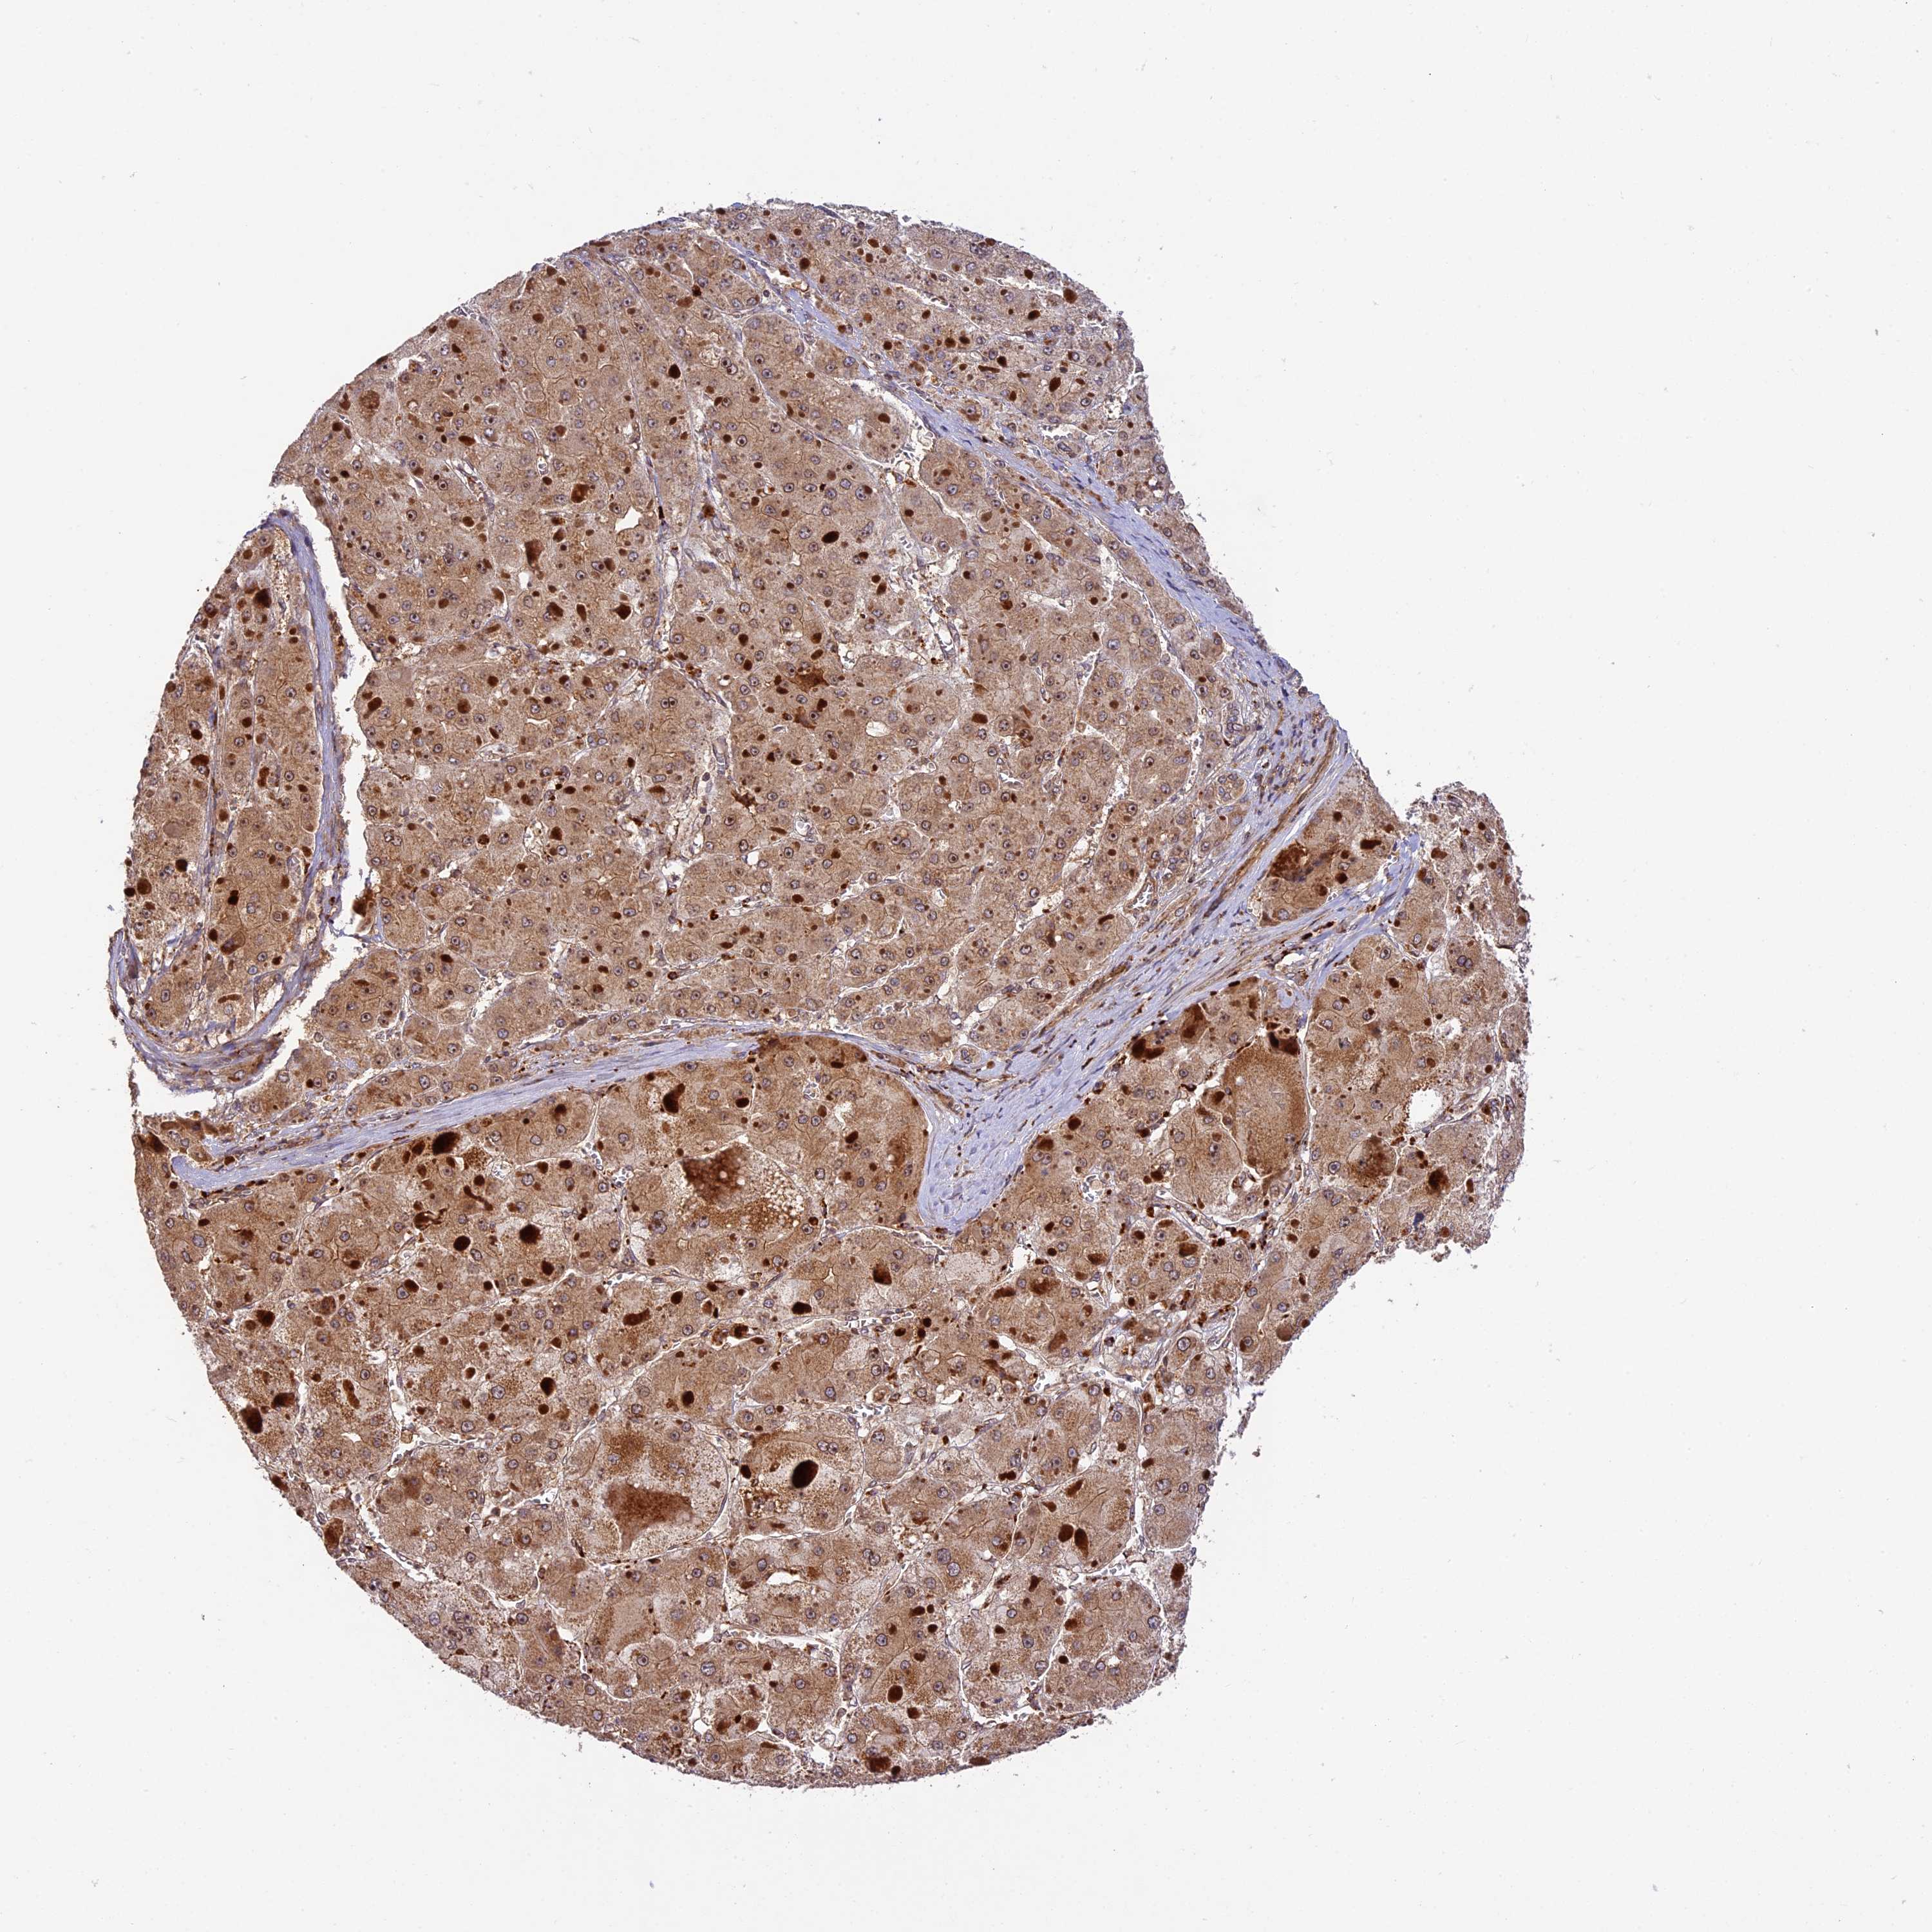

LIVER CANCER - Protein expressioni

A mouse-over function shows sample information and annotation data. Click on an image to view it in a full screen mode. Samples can be filtered based on level of antibody staining by selecting one or several of the following categories: high, medium, low and not detected. The assay and annotation is described here.

Note that samples used for immunohistochemistry by the Human Protein Atlas do not correspond to samples in the TCGA dataset.

Antibody stainingi

Antibody staining in the annotated cell types in the current human tissue is reported as not detected, low, medium, or high, based on conventional immunohistochemistry profiling in selected tissues. This score is based on the combination of the staining intensity and fraction of stained cells.

Each image is clickable and will lead to virtual microscopy that enables deeper exploration of all samples and also displays staining intensity scores, fraction scores and subcellular localization as well as patient and tissue information for each sample.

Antibody HPA039533

Antibody HPA040355

Staining

High

Medium

Low

Not detected

Intensity

Strong

Moderate

Weak

Negative

Quantity

>75%

75%-25%

<25%

None

Location

Nuclear

Cytoplasmic/membranous

Cytoplasmic/membranous,nuclear

Cholangiocarcinoma

Carcinoma, Hepatocellular, NOS